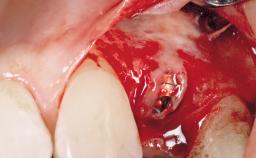

A 42-year-old female patient was referred to our clinic at the School of Dentistry of the University of São Paulo in November 2004, presenting a deficient restoration in the upper left central incisor. The clinical examination revealed no gingival retraction or any signs of gingival inflammation and, therefore, previous periodontal treatment was not considered. The patient presented a high lip line at full smile and a thin tissue biotype. This combination characterized a high-risk situation from an anatomic point of view, which required careful preoperative planning and cautious surgical execution.

Placement Protocol Immediate implant placement

Socket Integrity Sufficient, with intact bone walls

Bone Volume Sufficient, with intact walls

Risk of Complications High